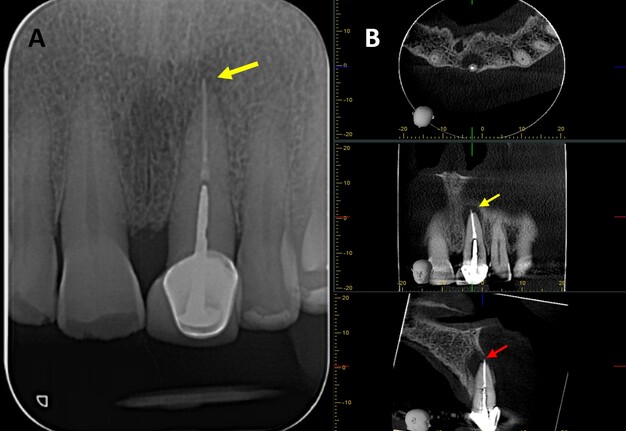

A 76-year-old male with no relevant medical history was referred to the postgraduate endodontics program (CES University Dental Clinic, Sabaneta, Colombia) for evaluation and management of tooth #21. Clinical examination showed a well-fitted metal-ceramic crown, normal probing, grade I mobility, tenderness to palpation and percussion, and fistula on the buccal mucosa. Cone beam computed tomography (CBCT) (J. Morita R100, Kyoto, Japan) at 90 mA, 8 kV, FOV 4 cm x 4 cm, and voxel size 0.5 mm showed a single canal with a post in the middle third of the root and extruded obturation material beyond the apex. The periapical lesion was visible on CBCT but not on periapical radiograph (Fig 1 A-B). The established diagnosis was a previously treated tooth with chronic apical abscess affecting tooth #21 (Fig 2-A). The proposed treatment plan was EMS, which was accepted by the patient after obtaining informed consent.

FIGURE 1. (A) Preoperative periapical radiograph of tooth #21, which the presence of a periapical radiolucency is not clearly. (B) Preoperative CBCT of tooth #21, presented in axial, coronal, and sagittal sections, reveals a hypodense area at the apical region consistent with a periapical lesion. The sagittal section demonstrates vestibular bone fenestration, as indicated by the red arrow. The yellow arrow denotes the presence of transapical obturation material in both the periapical radiograph and CBCT, as well as the existence of a post and prosthetic crown.

CBCT has been recommended for the diagnosis, planning and follow-up in endodontics, due to its three-dimensional imaging, which overcomes the limitations of traditional periapical radiograph (PR) [10, 11]. In this case, CBCT identified a periapical lesion that was not visible on PR and enabled more precise surgical planning. Furthermore, the tomographic follow-up findings suggested ongoing periapical healing. Compared to PR, it may have been mistakenly considered a complete healing, which supports the use of CBCT for longer-term follow-up of this case.